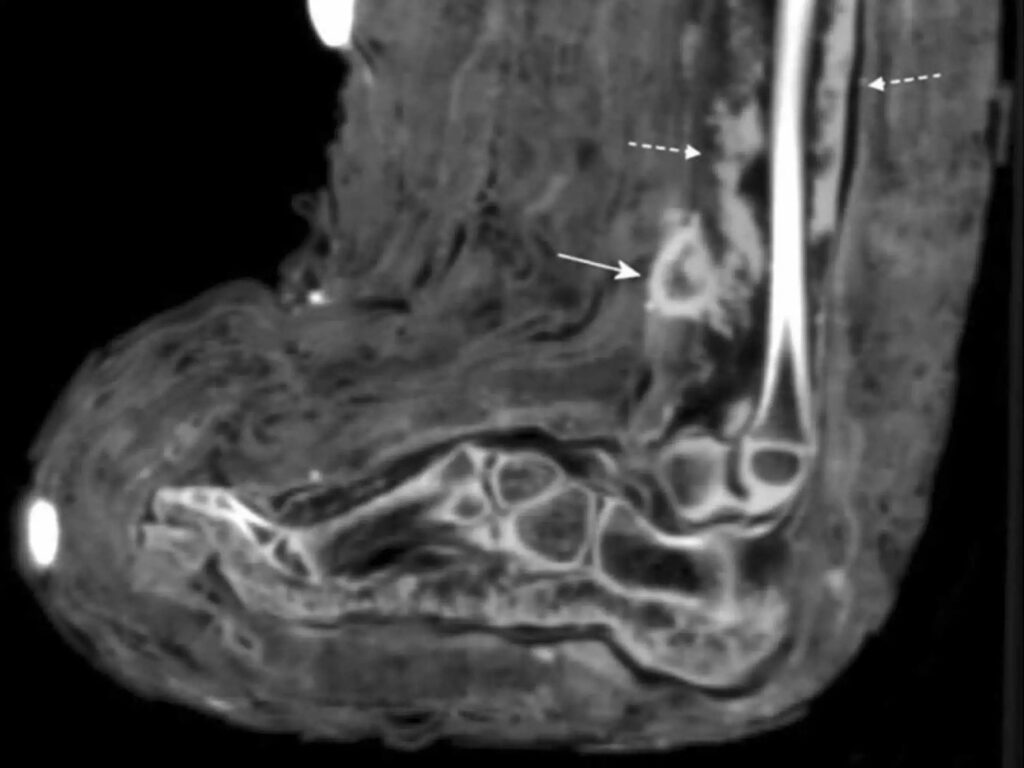

In this case, Zink said, the bandages were spotted while the scientists carried out routine CT scans of mummies, as can be seen in the scans below and annotated with the full-lined arrow. The wound appeared to have been infected when she died, as the scans showed signs of “pus,” Zink said. These signs of infection are marked by the dotted arrows in the scans below.

A side view of the mummy’s foot was seen in a CT scan.